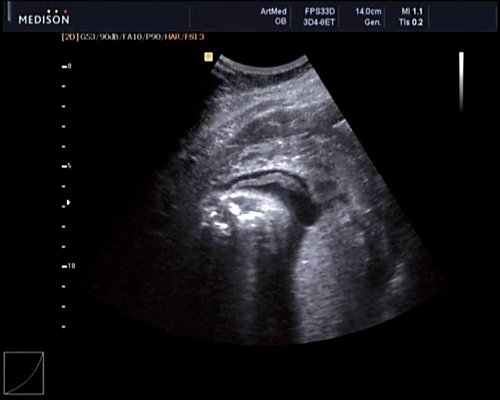

Данные КТ: к миелоцеле снизу и слева прилежит диспластичная дополнительная подвздошная кость, от которой отходят пучки мышечных волокон, идущие от ягодицы в дополнительную диспластичную нижнюю конечность, представленную аномально сформированными костно-хрящевыми структурами и пучками мышечных волокон. На расстоянии 19 мм от бифуркации аорты отходит подвздошная/бедренная артерия диаметром 1-1,5 мм, из которой дополнительная нижняя конечность получает кровоснабжение (рис. 3).

В возрасте 5 сут жизни ребенку выполнена операция: удаление дополнительной диспластичной нижней конечности, пластика дефекта позвоночного канала (рис. 4). При микроскопическом исследовании удаленной диспластичной нижней конечности определяются 4 слоя эпидермиса без мальпигиева слоя с выраженным кератозом, гиалиновые хрящи, мелкие кости с костным мозгом без патологических изменений. На основании данных гистологического исследования был поставлен диагноз плода в плоде. В послеоперационном периоде отмечалось просачивание ликвора через послеоперационные швы, которое удалось купировать наложением давящей повязки на послеоперационную рану и приданием ребенку положения на животе с опущенным головным концом.